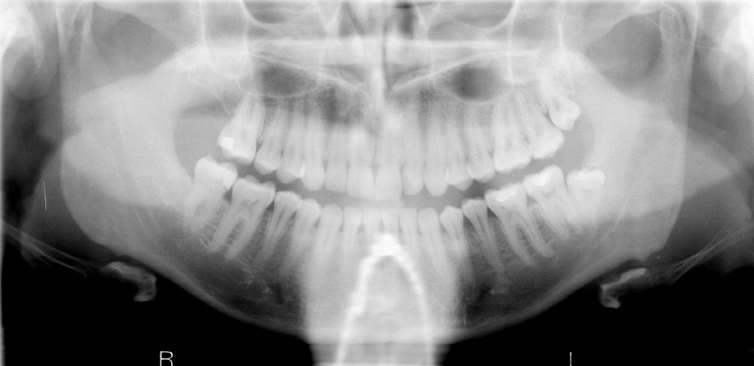

Q

What is wrong with this image?

A

necklace